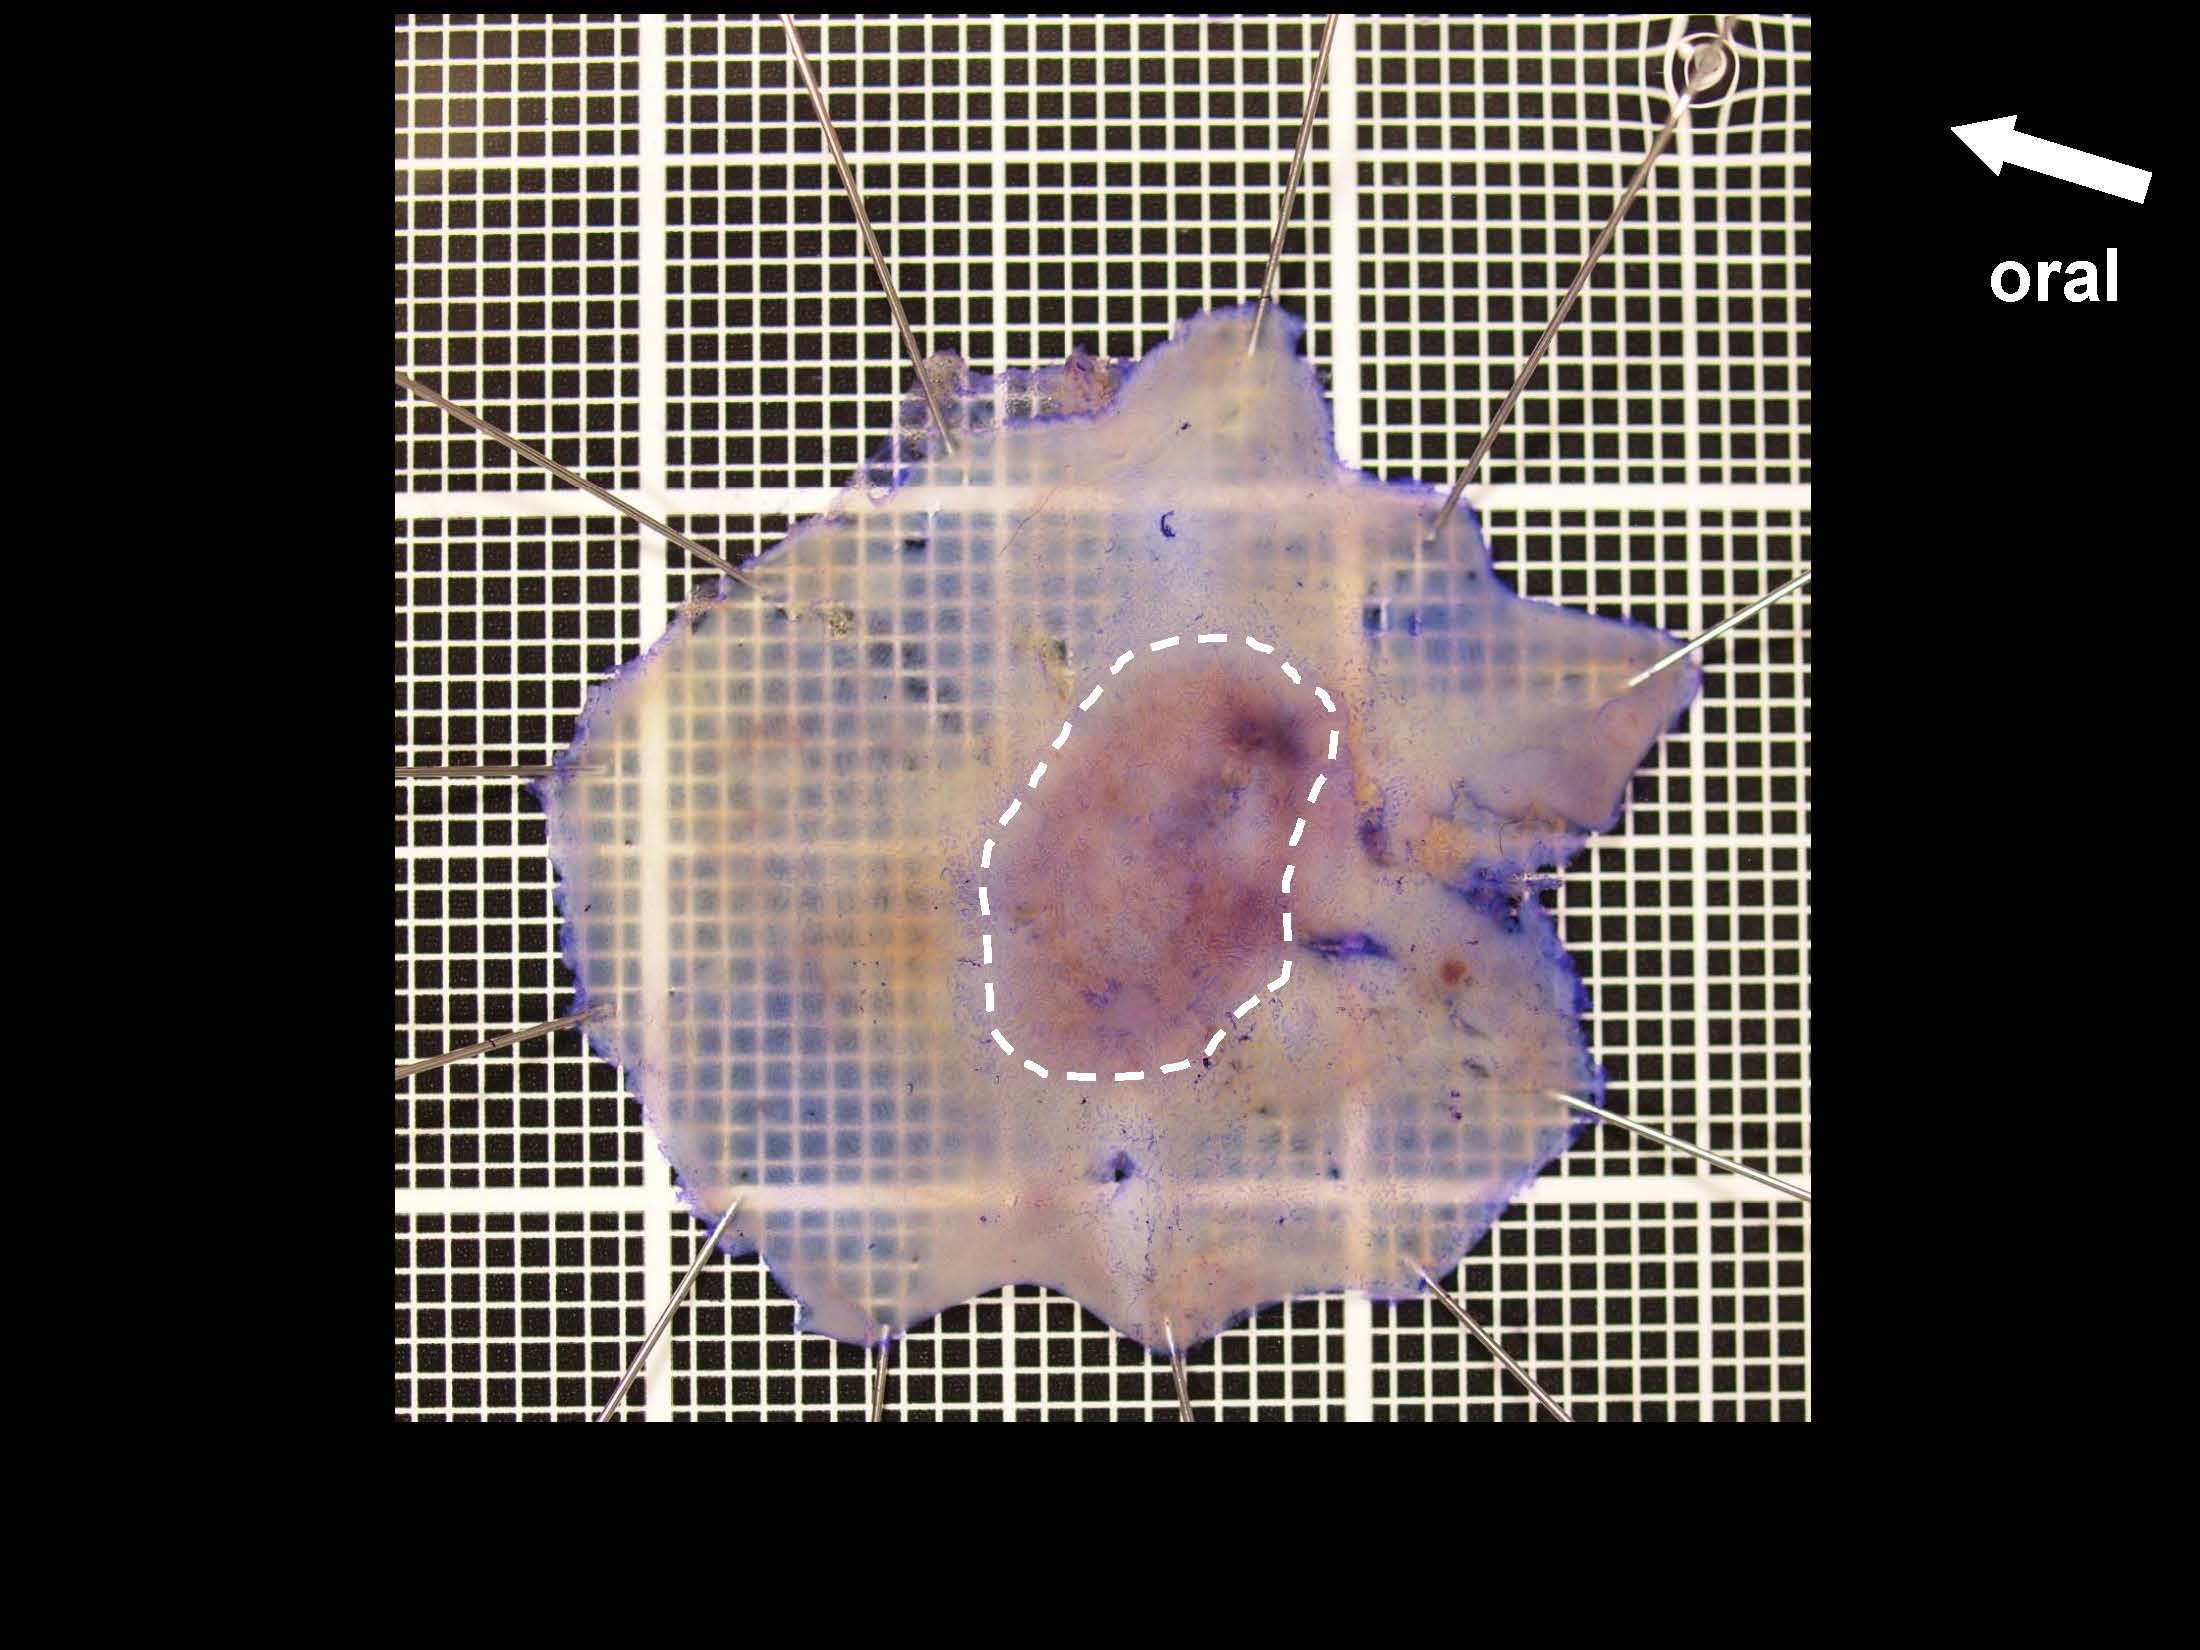

消化管Mapping~大腸~ 2021.10.27

消化管Mapping

消化管Mapping~大腸~

消化器内科

内視鏡検査・治療